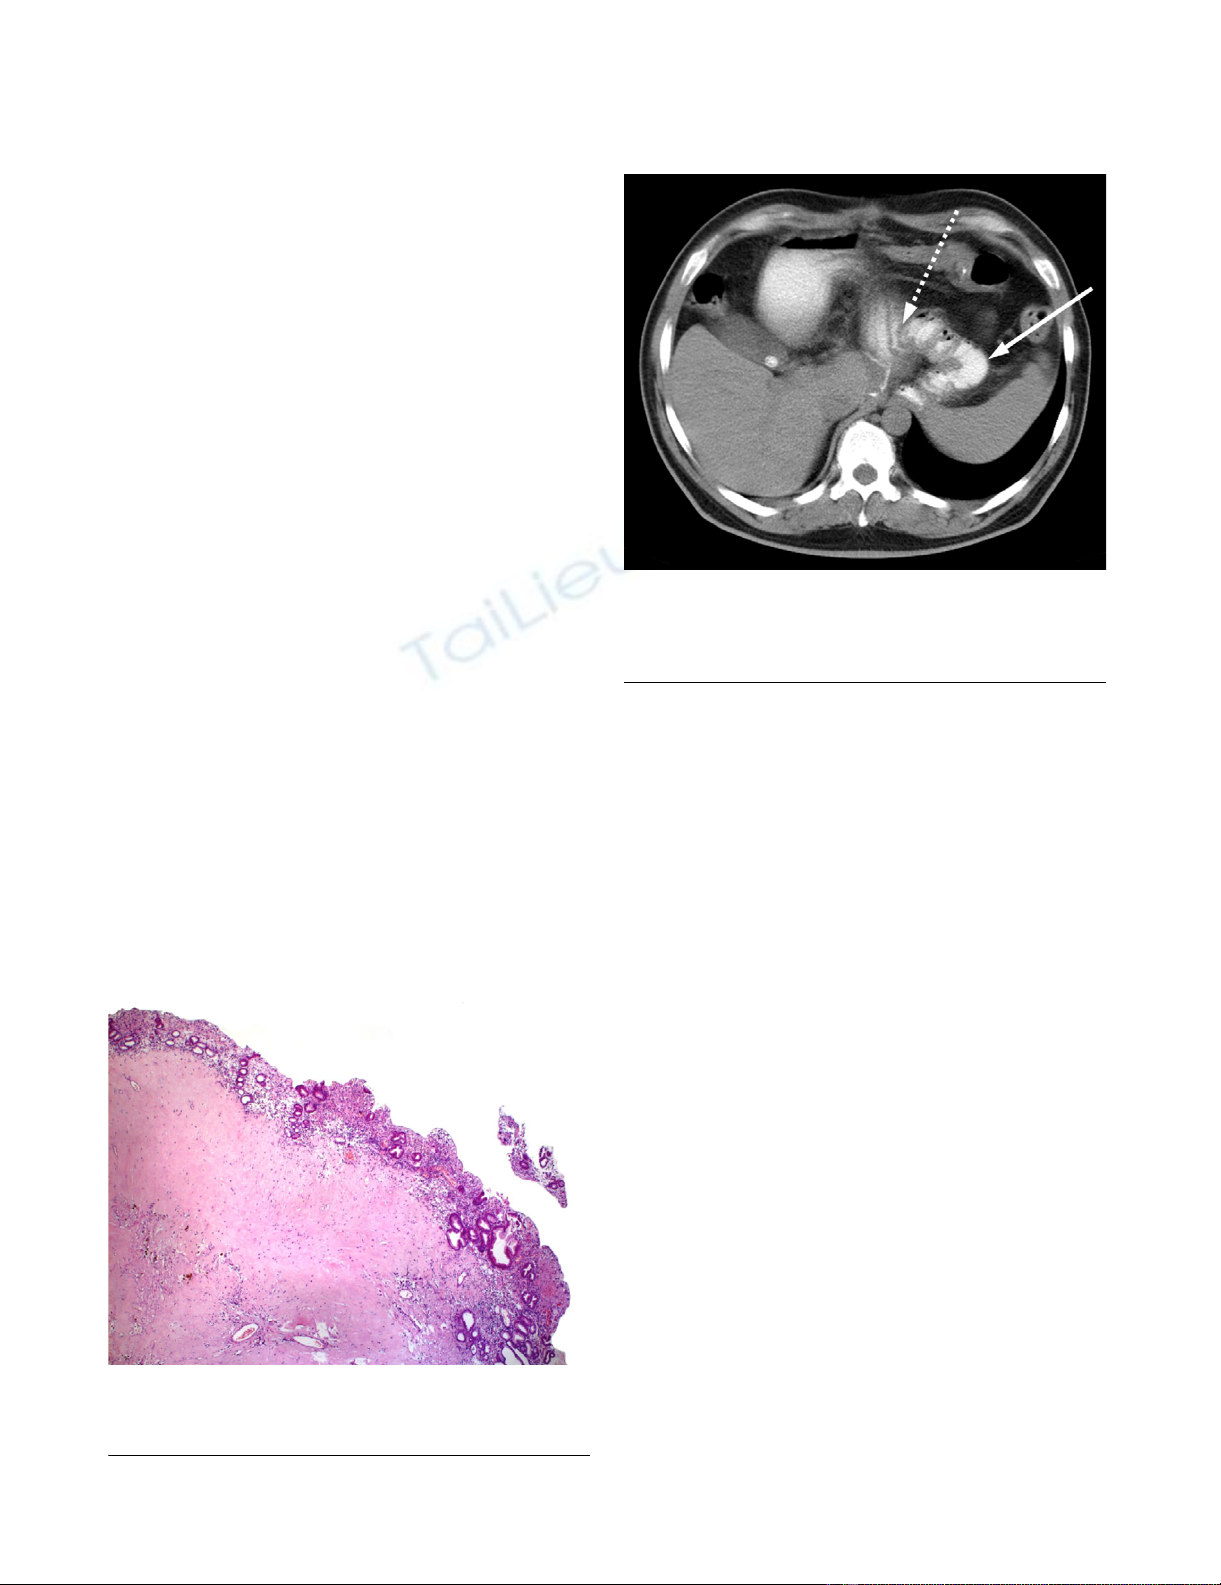

Postoperative CT-ScanFigure 6

Postoperative CT-Scan. Postoperative follow-up CT scan

after 18 months showing the jejunal interposition (gastro-

jejunostomy: interrupted arrow).

Histological examinationFigure 5

Histological examination. Postoperative histology with

regressive changes under normal gastric mucosa.

Histopathological examination of the resection specimen

confirmed a GIST with extensive regressive changes. The

tumor originated from the submucosal layers and

extended to the subserosa with a remaining diameter of

2.5 cm (figure 5). Tumor cells were still positive for c-Kit,

but the proliferation rate measured with Ki-67 expression

was less than 10%. Oral and aboral resection margins

were free of tumor cells as were eight perigastric lymph

nodes. Molecular pathology of exon mutation analysis

could not find a mutation in exons 9 and 11 of c-Kit nor

in exon 18 of PDGF receptor alpha. Thus the case was clas-

sified as 'wildtype'.